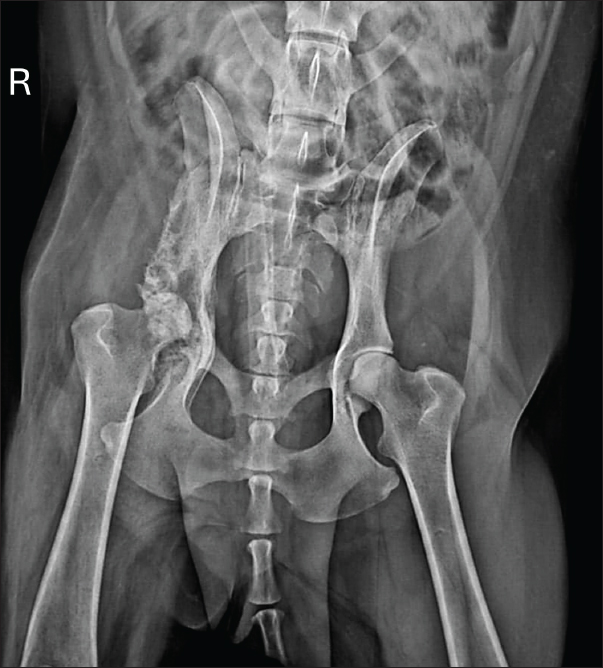

The dog showed significant clinical improvement, including reduced lameness and restored appetite, after 30 days of therapy. Pelvic radiographs revealed slight regression of periosteal proliferation and osteolytic areas (Fig. 4). Hematology and serum biochemistry remained within normal limits.

Fig. 4. Radiographic examination of the dog 30 days after initiation of itraconazole treatment, showing slight regression of periosteal bone proliferation and reduction of osteolytic areas.